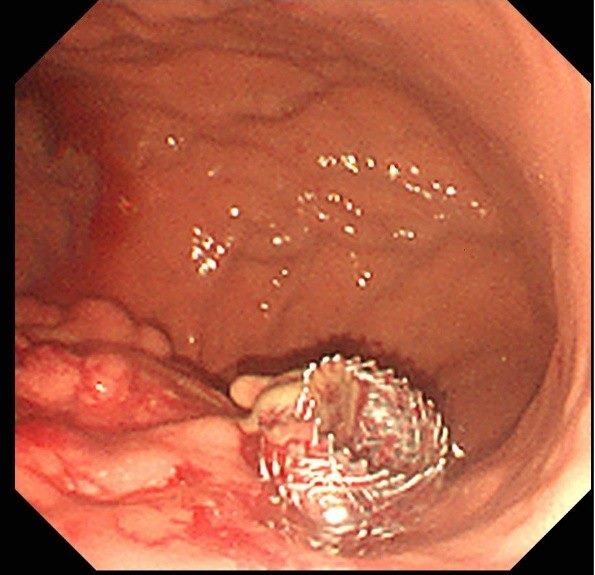

醫師黃柏翰說,這項微創手術透過內視鏡,將金屬支架精準地放置於胰臟病灶處並與胃內建立引流通道,有效排出壞死組織或囊液,成功避免了傳統外科手術的巨大創傷與高風險,為病患帶來治療新希望。

黃柏翰強調,這項新技術的成功,代表和平婦幼院區在處理複雜胰臟疾病的能力已邁入新里程碑。藉由內視鏡超音波精準定位後金屬支架的置放,能以更安全、更有效的方式,幫助那些因胰臟炎併發症而飽受折磨的病患。